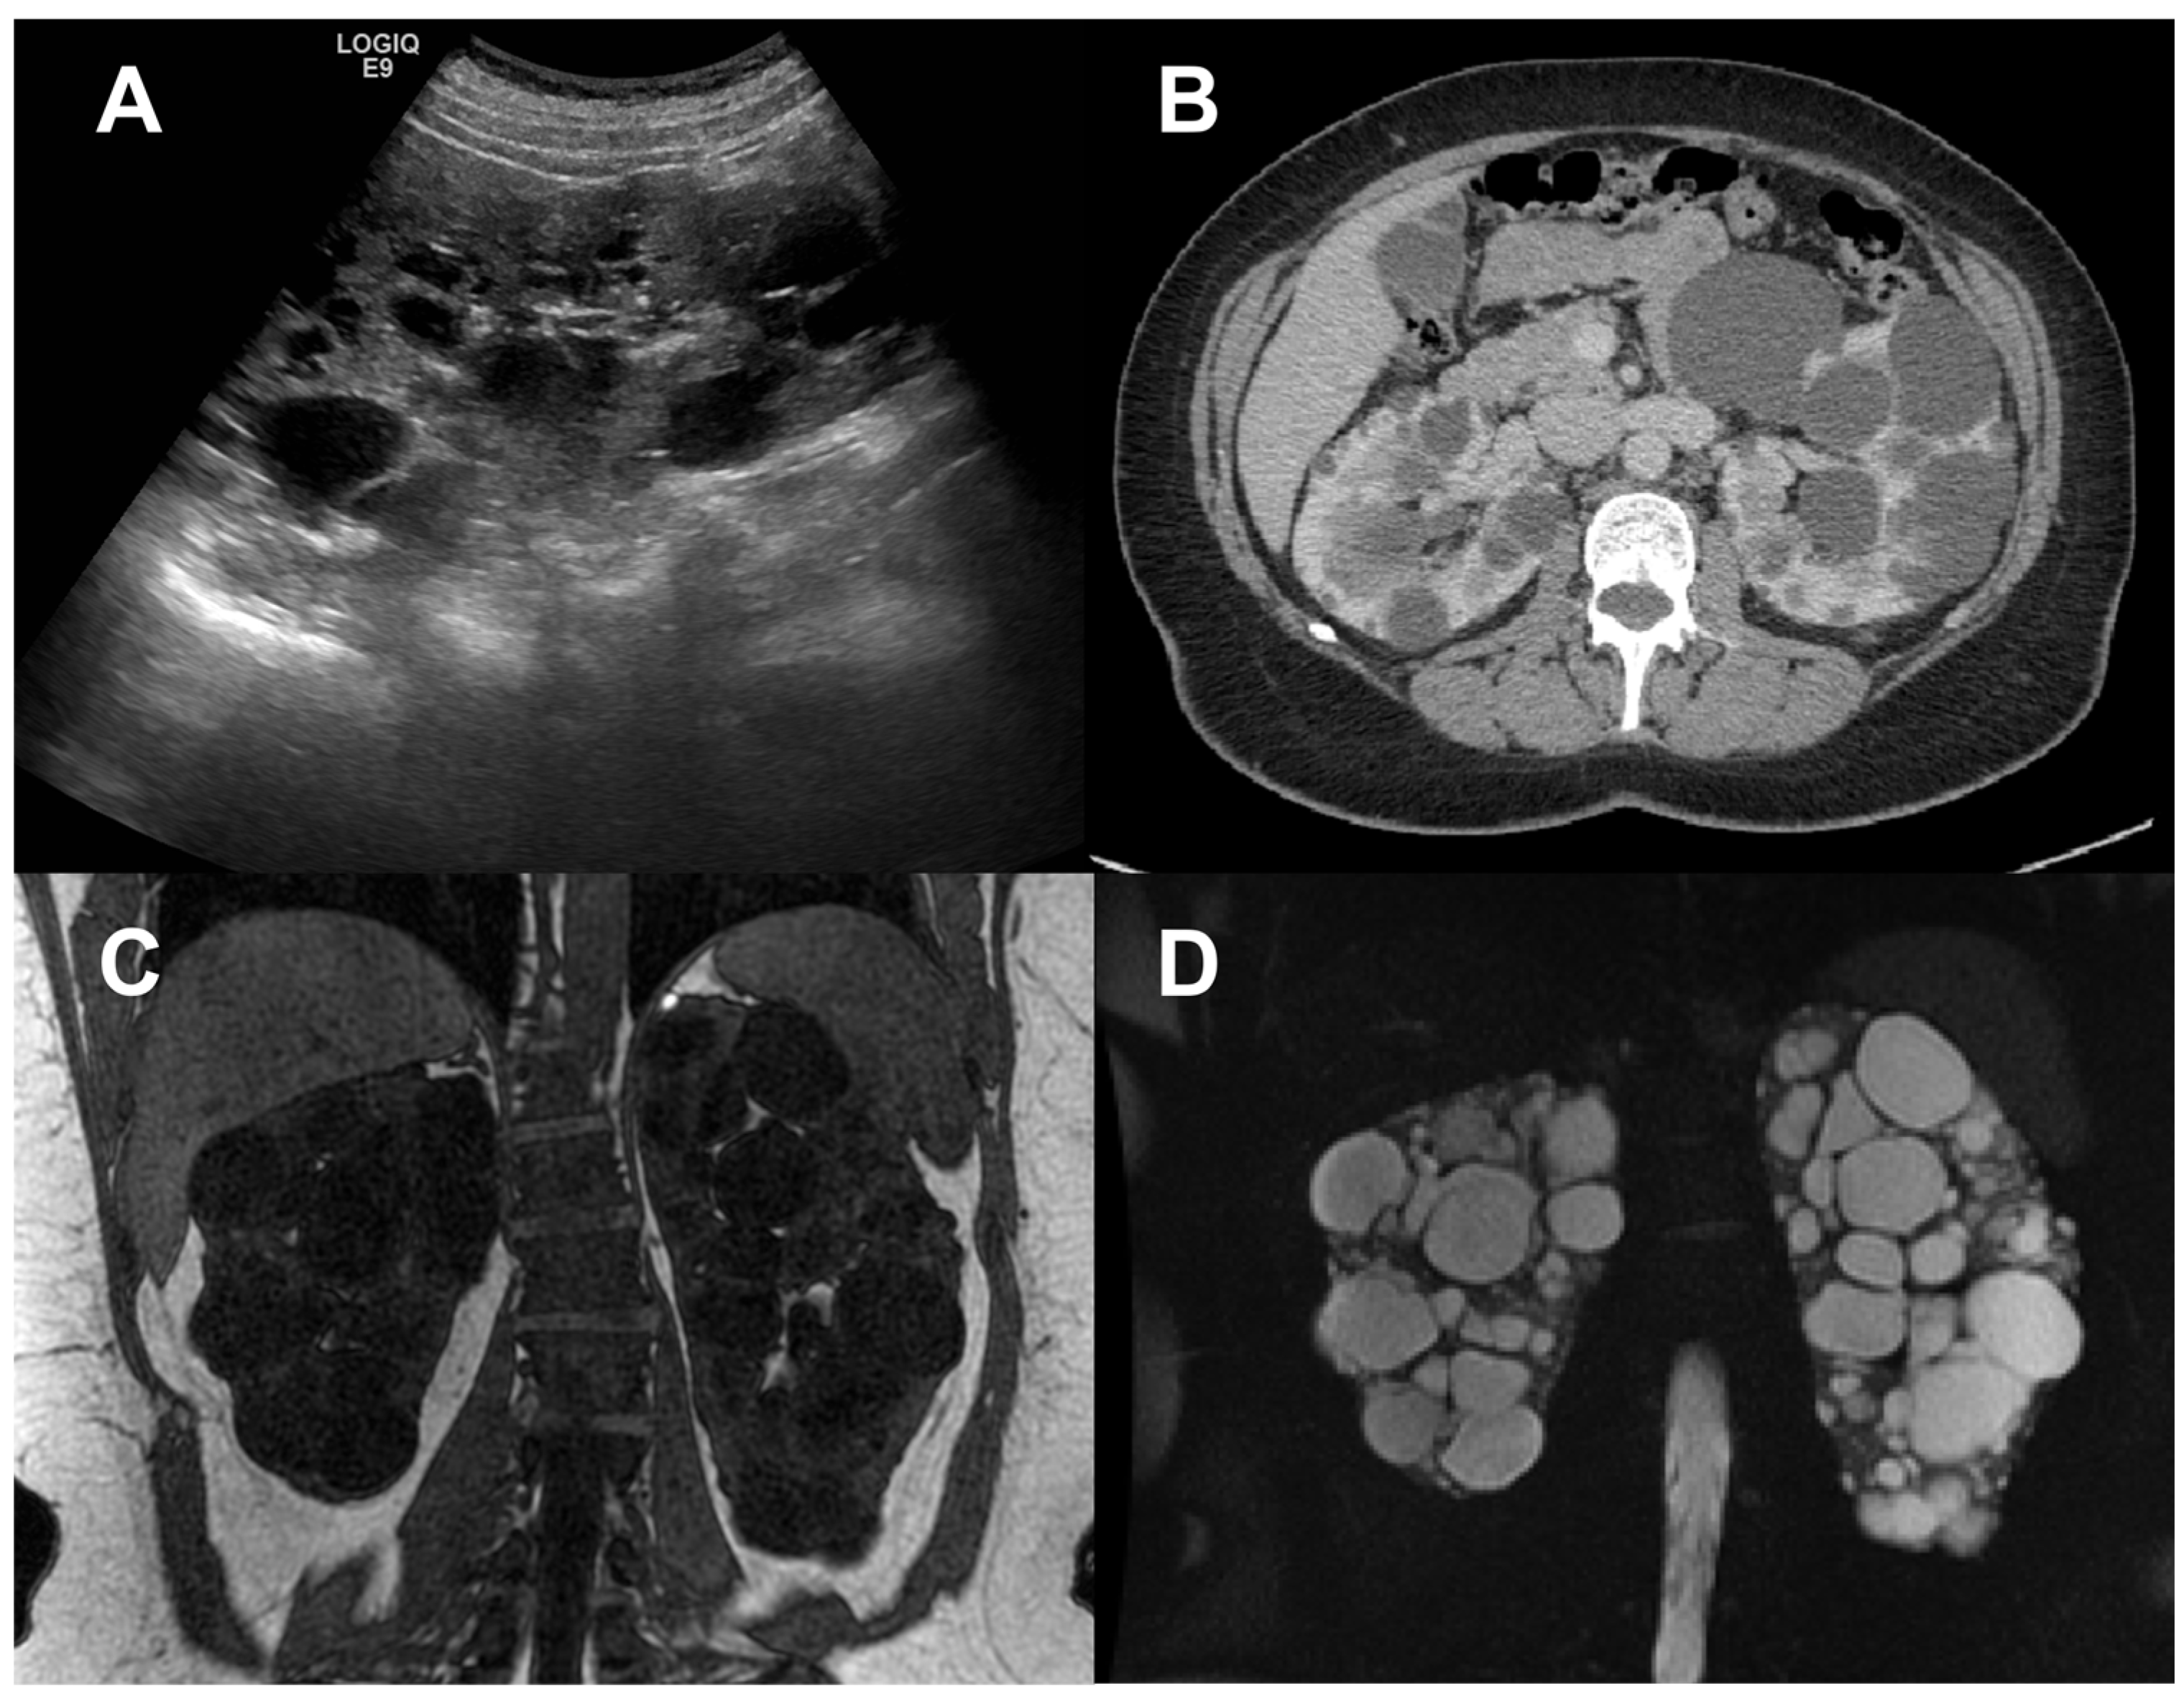

2. Total Kidney Volume

3. Cyst volume

4. Non-Cystic Tissue

5. Multiparametric Magnetic Resonance Imaging